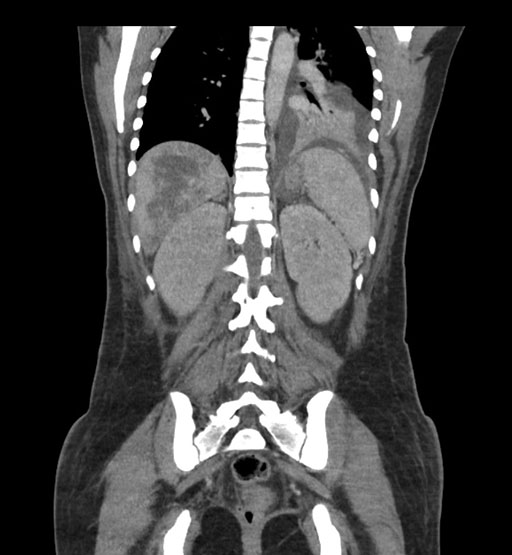

Coronal Venous

Imaging analysis

Based on initial findings, which issue(s) would you be most concerned about?